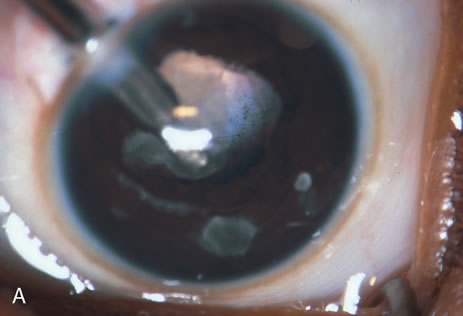

When the vitreous suction-cutting devices became available, they were quickly employed to remove cataracts in children. In addition to providing control of aspiration pressure and control of the flow of irrigation solutions, they also added the ability to remove some or all of the posterior lens capsule, even when the capsule had a thick fibrovascular stalk associated with persistent hyperplastic primary vitreous (PHPV) or a thick capsular plaque (Fig. 2). These fine-tip suction-cutting instruments provided sufficient control of the anterior chamber depth, thus permitting the surgeon to precisely open the posterior capsule and, if necessary, safely remove vitreous from the anterior chamber. Keech and co-workers,12 in a contemporaneous surgical series, showed that having the ability to remove the posterior lens capsule and perform an anterior vitrectomy reduced the need for secondary procedures from 75%, if the capsule was left intact, to 11% after capsulectomy and anterior vitrectomy. They found that when a large section of the posterior lens capsule was removed, it provided a lasting optical opening and reduced the requirement for additional surgery.